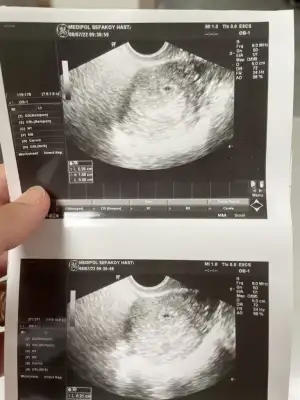

Kaç hafta kaç günlük canım şuan bebiş, tebrik ederimKızlar ben çıktım kontrolden. Çok şükür kalp atışını duyduk bebişi de gördükHer şey yolundaymış ve 7 haftalıkmış. Doğum tarihini de 3 Mart dedi. Kan ve idrar tahlili istedi vitaminlere vs bakmak için. Haftaya cuma tekrar gideceğim

Teşekkür ederim tam 7 haftalık dedi canım gün söylemediKaç hafta kaç günlük canım şuan bebiş, tebrik ederim![]()

Seninki de bı doğsun da inşallah zaman nasıl akıp gidiyor kendi gözlerinle görürsün canım, inşallah kucağımıza almak nasip olsun sağ salimAyy allah bagislasin o kucucuk fasulye tanesi koskoca adam olmus masallahbenim daha da belirgin ama sizinkine benziyor fasulye tanesi gibi benim bildigin sizin daha duzgun